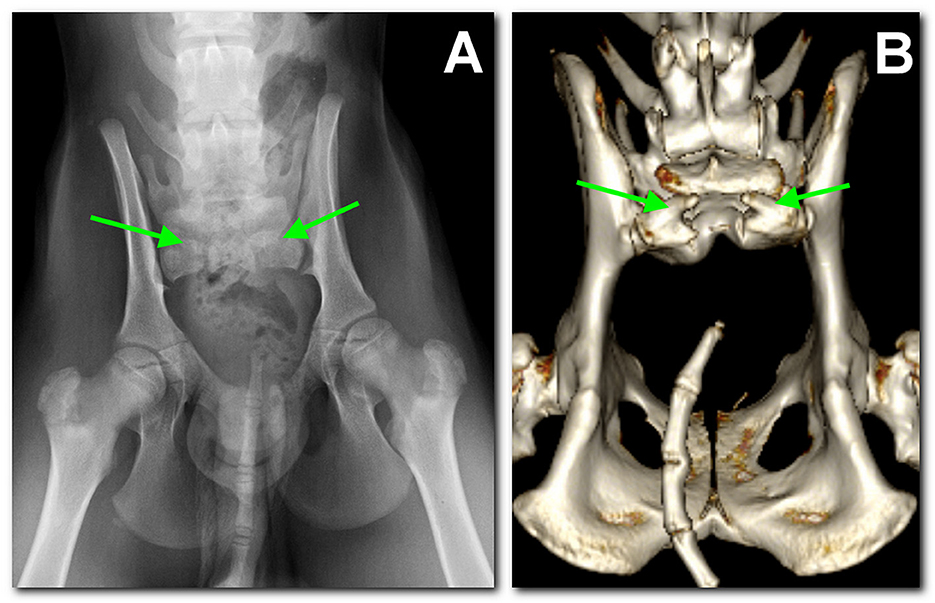

Dos perros bóxer de la misma camada fueron presentados a los 3 meses de edad por incontinencia urinaria y fecal. Ambos perros tenían una cola anormal que consistía en un pequeño muñón, un esfínter anal atónico y ausencia de reflejo y sensibilidad perineal. La evaluación neurológica fue indicativa de una lesión de la cola de caballo o médula espinal sacra. La radiología y la tomografía computarizada de la columna vertebral mostraron hallazgos similares en los dos perros que eran indicativos de agenesia sacra. De hecho, tenían 6 vértebras lumbares seguidas de una vértebra lumbosacra transitoria, que carecía de una apófisis espinosa completa, y una vértebra hipoplásica que portaba 2 apófisis transversas sacras hipoplásicas como único remanente del hueso sacro. Las vértebras caudales estaban ausentes en uno de los perros. En la resonancia magnética, un perro tenía un saco dural que ocupaba todo el canal espinal y terminaba en una estructura de grasa subfascial. En el otro perro, el saco dural terminaba en una estructura quística extracanalar, subfascial, bien definida, que se comunicaba con el espacio subaracnoideo y era compatible con un meningocele. La agenesia sacra, es decir, la ausencia parcial o completa de los huesos sacros, es un defecto del tubo neural que se reporta ocasionalmente en humanos con espina bífida oculta. La agenesia sacra se ha descrito en medicina humana y veterinaria en asociación con afecciones como el síndrome de regresión caudal, el perosomus elumbis y el síndrome de Currarino. Estos defectos del tubo neural son causados por factores genéticos y/o ambientales. A pesar de la investigación genética exhaustiva, no se pudieron encontrar variantes candidatas en genes con impacto funcional conocido en el desarrollo óseo o sacro en los perros afectados. Hasta donde saben los autores, este es el primer informe que describe una agenesia sacra similar en dos perros bóxer emparentados.